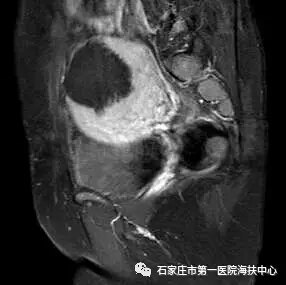

海扶术后磁共振图像